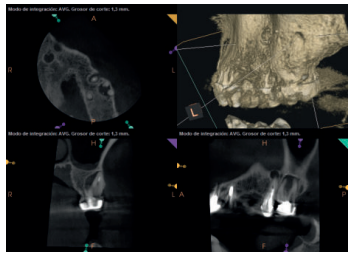

A los seis meses el paciente acudió a revisión sin ninguna sintomatología, tanto a nivel anterior como posterior. En las radiografías periapicales se apreció una disminución en el tamaño de las lesiones periapicales radiolúcidas preexistentes (Figuras 10 y 11). Dado que faltaba tratar la lesión del 25, se realizó CBCT de control donde se comprobó la mejoría a nivel del 26 (Figura 12), por lo que se programó la microcirugía del 25.

Una vez realizada la microcirugía del 25, el paciente no volvió a presentar ninguna sintomatología y las tomografías de control a 12 meses (en 25) y a 18 meses en los dientes restantes mostraron la regeneración de las lesiones periapicales radiolúcidas preexistentes en todos los dientes tratados (Figuras 13 a 16).

Se realizaron controles radiológicos a los 6, 12 y 18 meses mediante CBCT, apreciándose ausencia de sintomatología y reversión del cuadro infeccioso crónico, así como progresividad y estabilidad en la regeneración ósea apical. A nivel del 21 se aprecia radioopacidad periapical, sin pérdida de volumen, y ausencia de invasión del espacio preservado por el tejido blando circundante. Si bien algunos autores han utilizado plasma rico en factores de crecimiento (PRGF) asociado a Bio-Oss® y Bio-Gide® en casos similares al nuestro, hemos obtenido un resultado adecuado sin aplicar PRGF como técnica complementaria13.